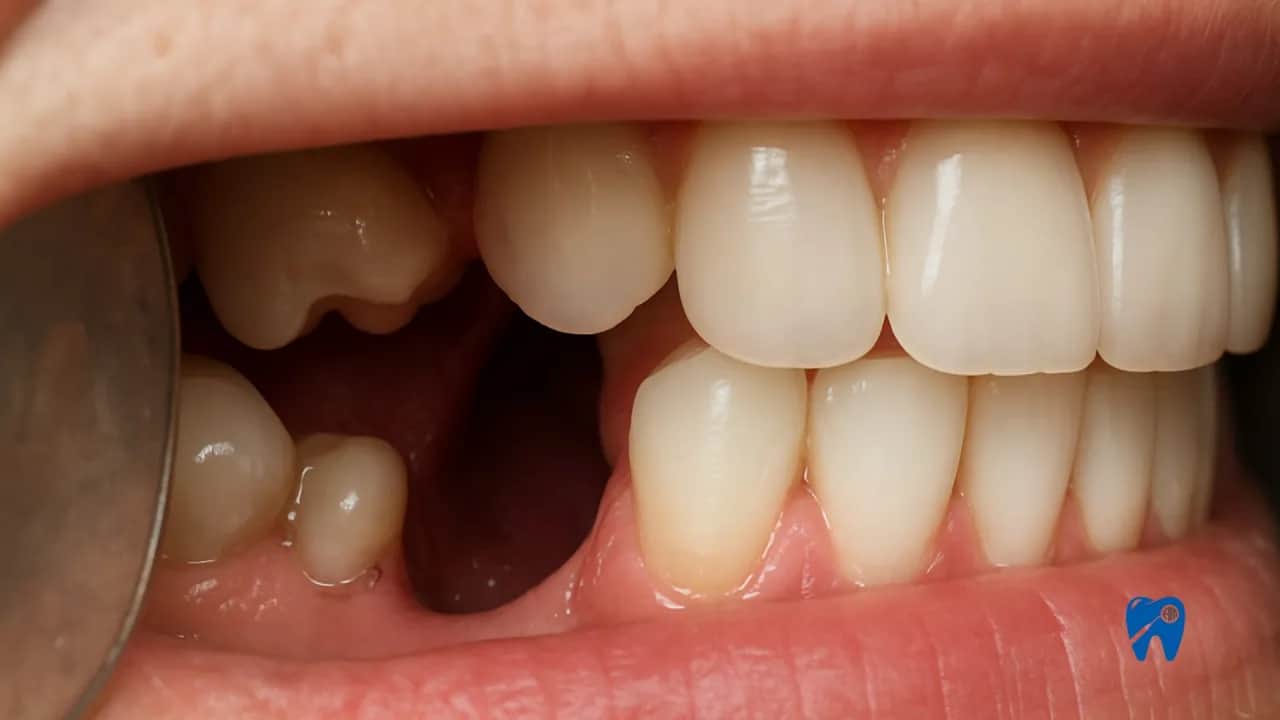

Pozostawiony korzeń zęba to tykająca bomba poznaj realne zagrożenia

Zawsze podkreślam moim pacjentom, że pozostawiony korzeń zęba to nie tylko kwestia estetyki czy dyskomfortu. To przede wszystkim poważne zagrożenie dla zdrowia, które może prowadzić do szeregu nieprzyjemnych, a nawet groźnych konsekwencji. Organizm traktuje taki korzeń jak ciało obce i otwarte wrota dla bakterii. Oto główne zagrożenia, z którymi możemy się spotkać:

- Zanik kości: Przewlekły stan zapalny wokół pozostawionego korzenia prowadzi do stopniowej degradacji kości szczęki lub żuchwy. To z kolei może znacząco utrudnić, a nawet uniemożliwić w przyszłości leczenie implantologiczne, jeśli pacjent zdecyduje się na odbudowę brakującego zęba.